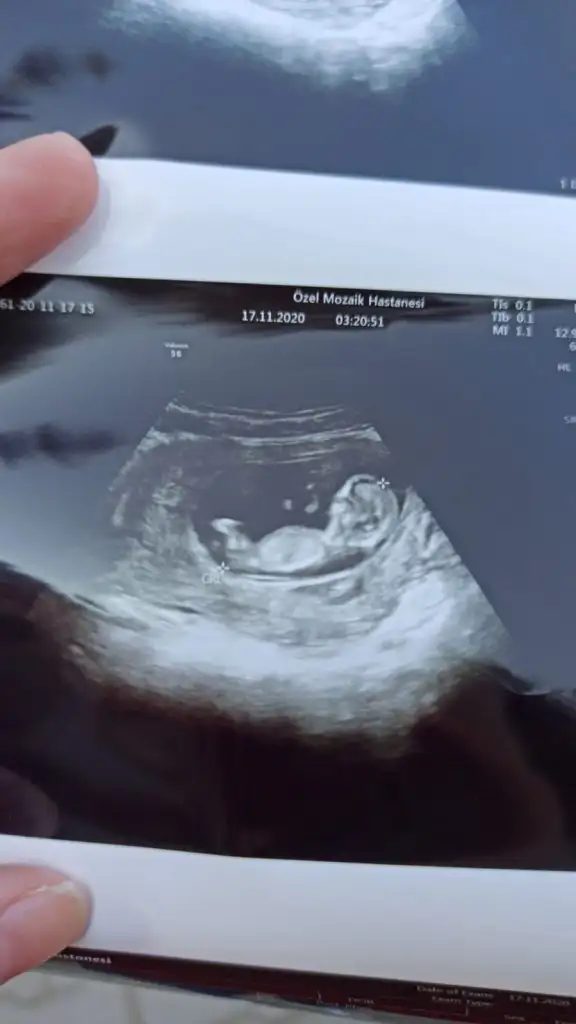

Bugun cinsiyetimizi öğrendik kizim geliyormus hayirlisiyla bakalim

Sağlıkla gelsinBugun cinsiyetimizi öğrendik kizim geliyormus hayirlisiyla bakalim

Evet erkek pipi orda duruyor yine benim dediğimMerhabaIkra meyra 11+4 görüntüye erkek gibi demiştiniz, doktorum kız gibi demişti ama kesin değildi. Bugün tekrar gittim 16+0 ultrason da 17 haftalık çıktı erkek diyor ama ben çok güvenemedim.Ultrason görüntüsü bacak arası mı çok anlamıyorum yorumlayabilir misin? Şimdiden teşekkürler

Kiz görünüyor başka USG varsa paylaşın 11 12 13 haftalar olmalıBenimkisinede bakar misiniz?Eki Görüntüle 2723115 Eki Görüntüle 2723116